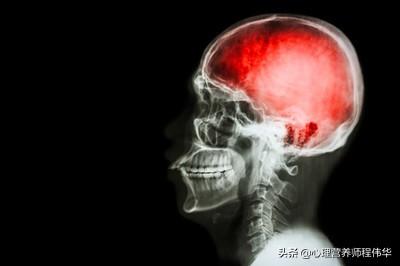

脳血栓症とは、血管壁の肥厚、内腔の狭小化、または閉塞をもたらす局所的な血管疾患および二次的な血栓症による脳動脈の局所神経障害の症状および徴候を指し、その結果、脳への局所的な血流が減少するか、血液供給が遮断され、脳組織の虚血、低酸素、壊死が生じる。

脳血栓症は脳梗塞とも呼ばれ、脳の血管が狭くなり、脳への血液供給が著しく不足することで、この血管が供給する部位に虚血や壊死が生じ、この部位を担当する機能に異常が生じる。例えば、体性運動野や言語中枢に梗塞が生じると、四肢の運動障害や言語障害が局所的に現れる。

脳血栓症は、脳に血液を供給している動脈の動脈硬化により血管が狭くなったり閉塞したりすることで発症し、脳梗塞や脳卒中と呼ばれることが多い。一般的な症状としては、不明瞭な発語、理解不能な発語、一貫性のない発語、手足のしびれ、口が曲がるなどがあります。脳血栓の形成は、ほとんどが大動脈の動脈硬化と血管プラーク形成によるものです。

脳血栓は主に動脈硬化、血液組成の変化、血圧異常によって形成される。糖尿病は、主に高エネルギー、高脂肪、高糖分食などの不摂生な生活習慣の結果として発症する。

脳血栓はどのようにして起こるのか?

3.血液成分の変化、血管病変の内膜の粗さにより、血液中の血小板が付着しやすくなり、蓄積しやすくなり、ペンタゾシンなどの化学物質が多く放出されるようになる。血液中のリポ蛋白、コレステロール、フィブリノゲン含量が増加すると、血液の粘度が増し、血液の流れが悪くなる。また、白血病、赤血球増加症などの血液疾患や血液凝固能の亢進に影響するさまざまな因子によって、脳血栓症が起こりやすくなる。

一定の関係がある。脳血栓症の原因は複雑で、高血圧、糖尿病、高脂血症、高ホモシステイン、多量喫煙、アルコール依存症、塩分過多、油分過多の食事、運動不足、肥満などが原因で、心血管や脳血管が障害され、血小板凝集能亢進、血管壁への炎症性細胞の接着が起こり、小血管の動脈硬化や動脈硬化が起こり、脳血栓が形成される。

長期的な食事構造の不合理のために、あまりにも多くの細かい穀物、大きな魚や肉、人間の吸収の変化をもたらし、人体はあまりにも多くのデリケートなデンプンを消費し、その結果、高速グルコース変換、膵島の消化負担をもたらし、インスリンの分泌が不十分または比較的不十分または遅延のために、人体の血糖値が上昇し、あらゆる種類の臓器が砂糖水に浸し、時間をかけてゆっくりと合併症が現れた。したがって、糖尿病の予防だけでなく、適切な粗い穀物、より多くの野菜、より多くの繊維は、消化の速度を遅くする。開脚に加えて、砂糖を下げるために運動する。脳血栓症の形成の根本的な原因も同じで、不合理な食事構造のため、体内のコレステロールが増加し、LDLが増加し、時間が経つにつれて、血管内のプラークの形成、血液の流れで、その結果、うっ血、血栓の形成。つまり、脳血栓症であれ糖尿病であれ、その人の日頃の食生活と無関係ではないのである。